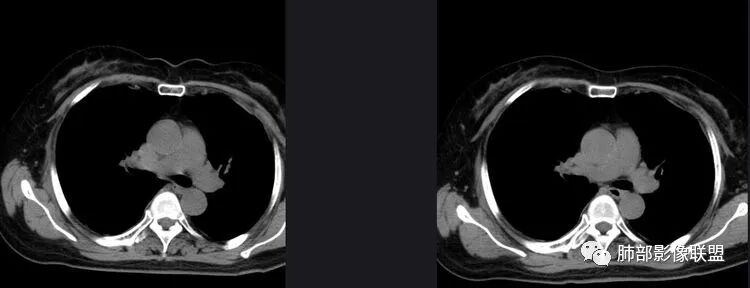

以下是两个时间点左右对比

2019.11.26  👇                           2020.01.20👇                                            2019.11.26片

2020.01.20片

2.早期CT表现左肺上叶不规则团块影,呈混合密度,以实性密度为主,但整体密度偏低,周围隐约见磨玻璃密度影。

边缘不规则,前内侧缘见小叶间隔限制(注意,并非典型深分叶),病灶外侧细长毛刺,病灶内有小空泡及空气支气管征,有胸膜牵拉征象。

上述征象均提示病灶为恶性病灶,但边缘特征及空气支气管征似乎有别于常见的浸润性腺癌及MALT。

3.复查影像显示病灶整体大小变化不明显,其内空泡消失,但是周围磨玻璃影趋于似清非清,整体病灶收缩力中等偏弱,均提示粘液腺癌的可能性大。